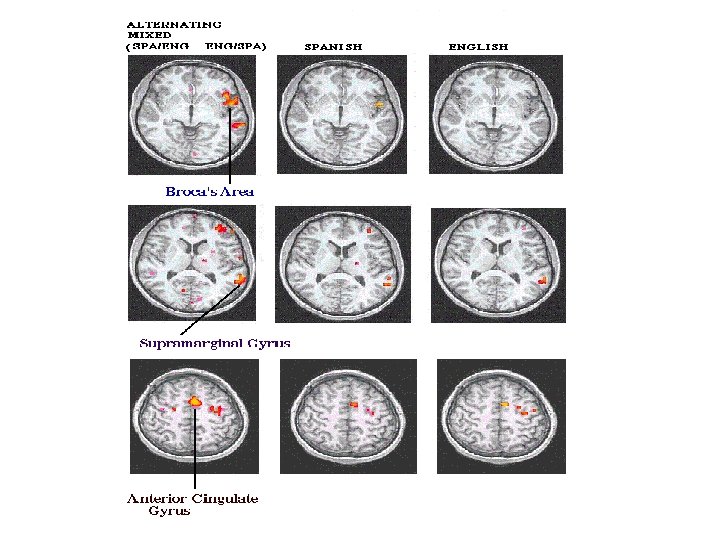

Funktsionaalne magnetresonantskuvamine f. MRI • Põhimõte sama kui MRI-l • Uuritakse aju aktiivsust TEGUTSEMISEL (lugemine, piltide vaatamine, helide kuulamine) • Arvestab aju verevoolu ja hapnikutarbimist • Näitab ajupiirkondade aktiivsust kolmemõõtmeliselt